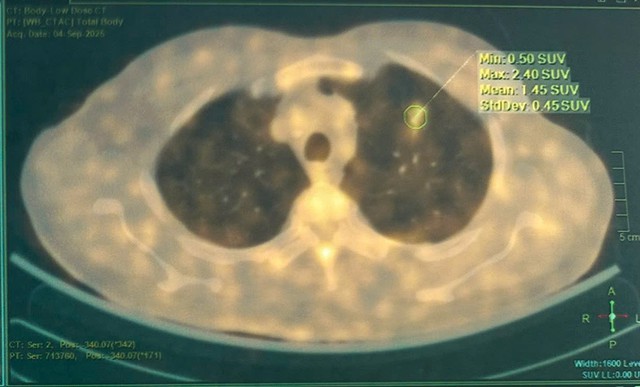

Trí tuệ nhân tạo hỗ trợ chẩn đoán ung thư phổi "Make in Bạch Mai" phân tích hình ảnh chẩn đoán (CT scan), giúp phát hiện sớm các nốt tổn thương phổi, nguy cơ ung thư

Tại hội thảo, giải pháp trí tuệ nhân tạo hỗ trợ chẩn đoán ung thư phổi "Make in Bạch Mai" được các bác sĩ giới thiệu. Đây là công nghệ thông minh do Bệnh viện Bạch Mai phát triển, sử dụng trí tuệ nhân tạo để phân tích hình ảnh chẩn đoán (CT scan), giúp phát hiện sớm các nốt tổn thương phổi, tăng độ chính xác và tối ưu hóa thời gian chẩn đoán.

PGS-TS Phạm Cẩm Phương, Giám đốc Trung tâm Y học hạt nhân và ung bướu (Bệnh viện Bạch Mai), cho biết, bệnh viện đang triển khai mô hình kết hợp giữa AI, chuyên gia đầu ngành và hội chẩn đa chuyên khoa. Không chỉ dừng lại ở phát hiện bệnh, các bác sĩ hướng tới điều trị cá thể hóa ngay từ đầu, dựa trên đặc điểm di truyền của từng bệnh nhân.